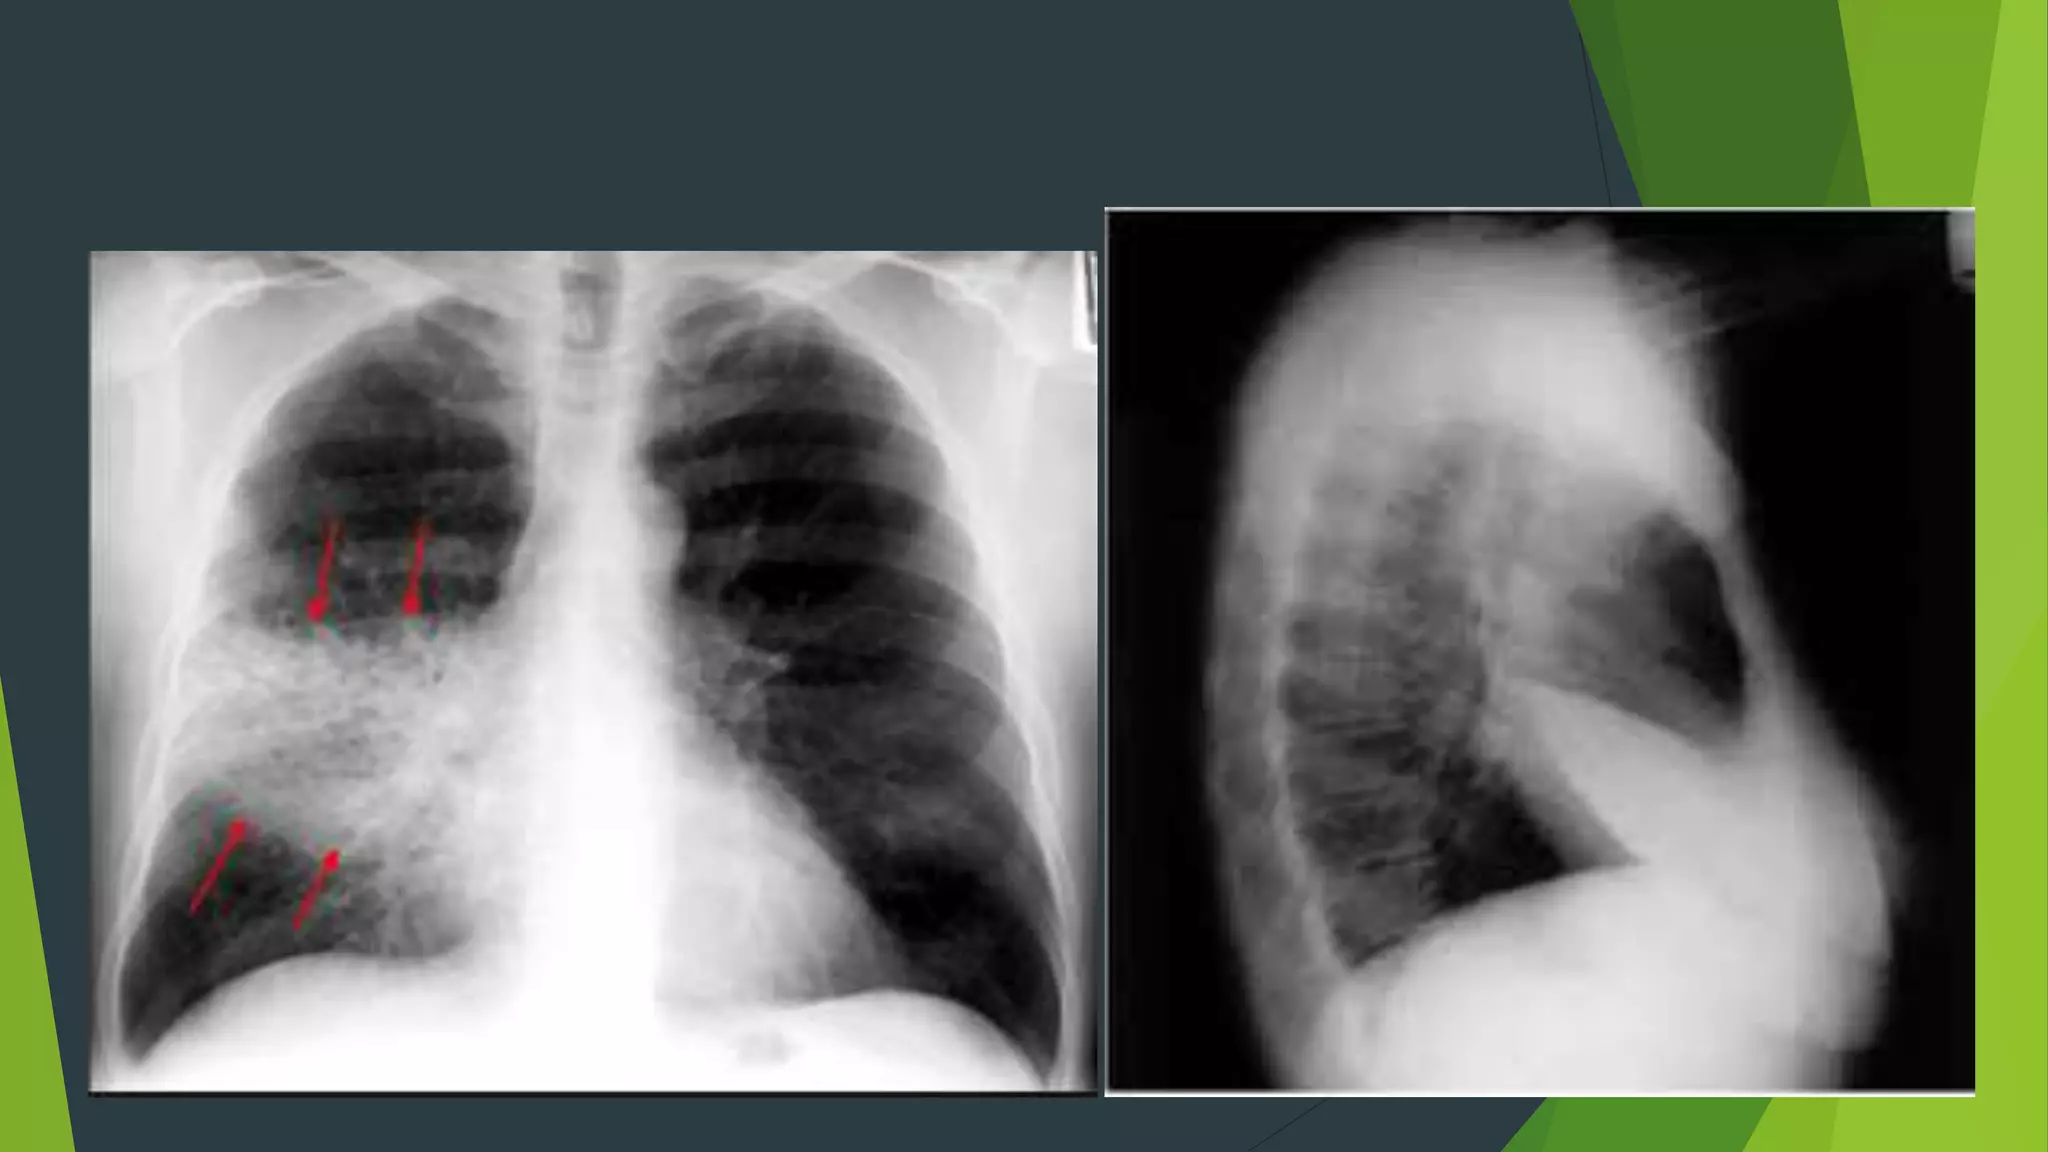

Tràn dịch màng phổi tự do

 Hình ảnh mờ đậm thuần

nhất , không có hình ảnh

nhu mô phổi.

 Mất góc sườn hoành

 Có đường cong Damoiseau

TDMP lượng vừa ( Đường

cong Damoiseau